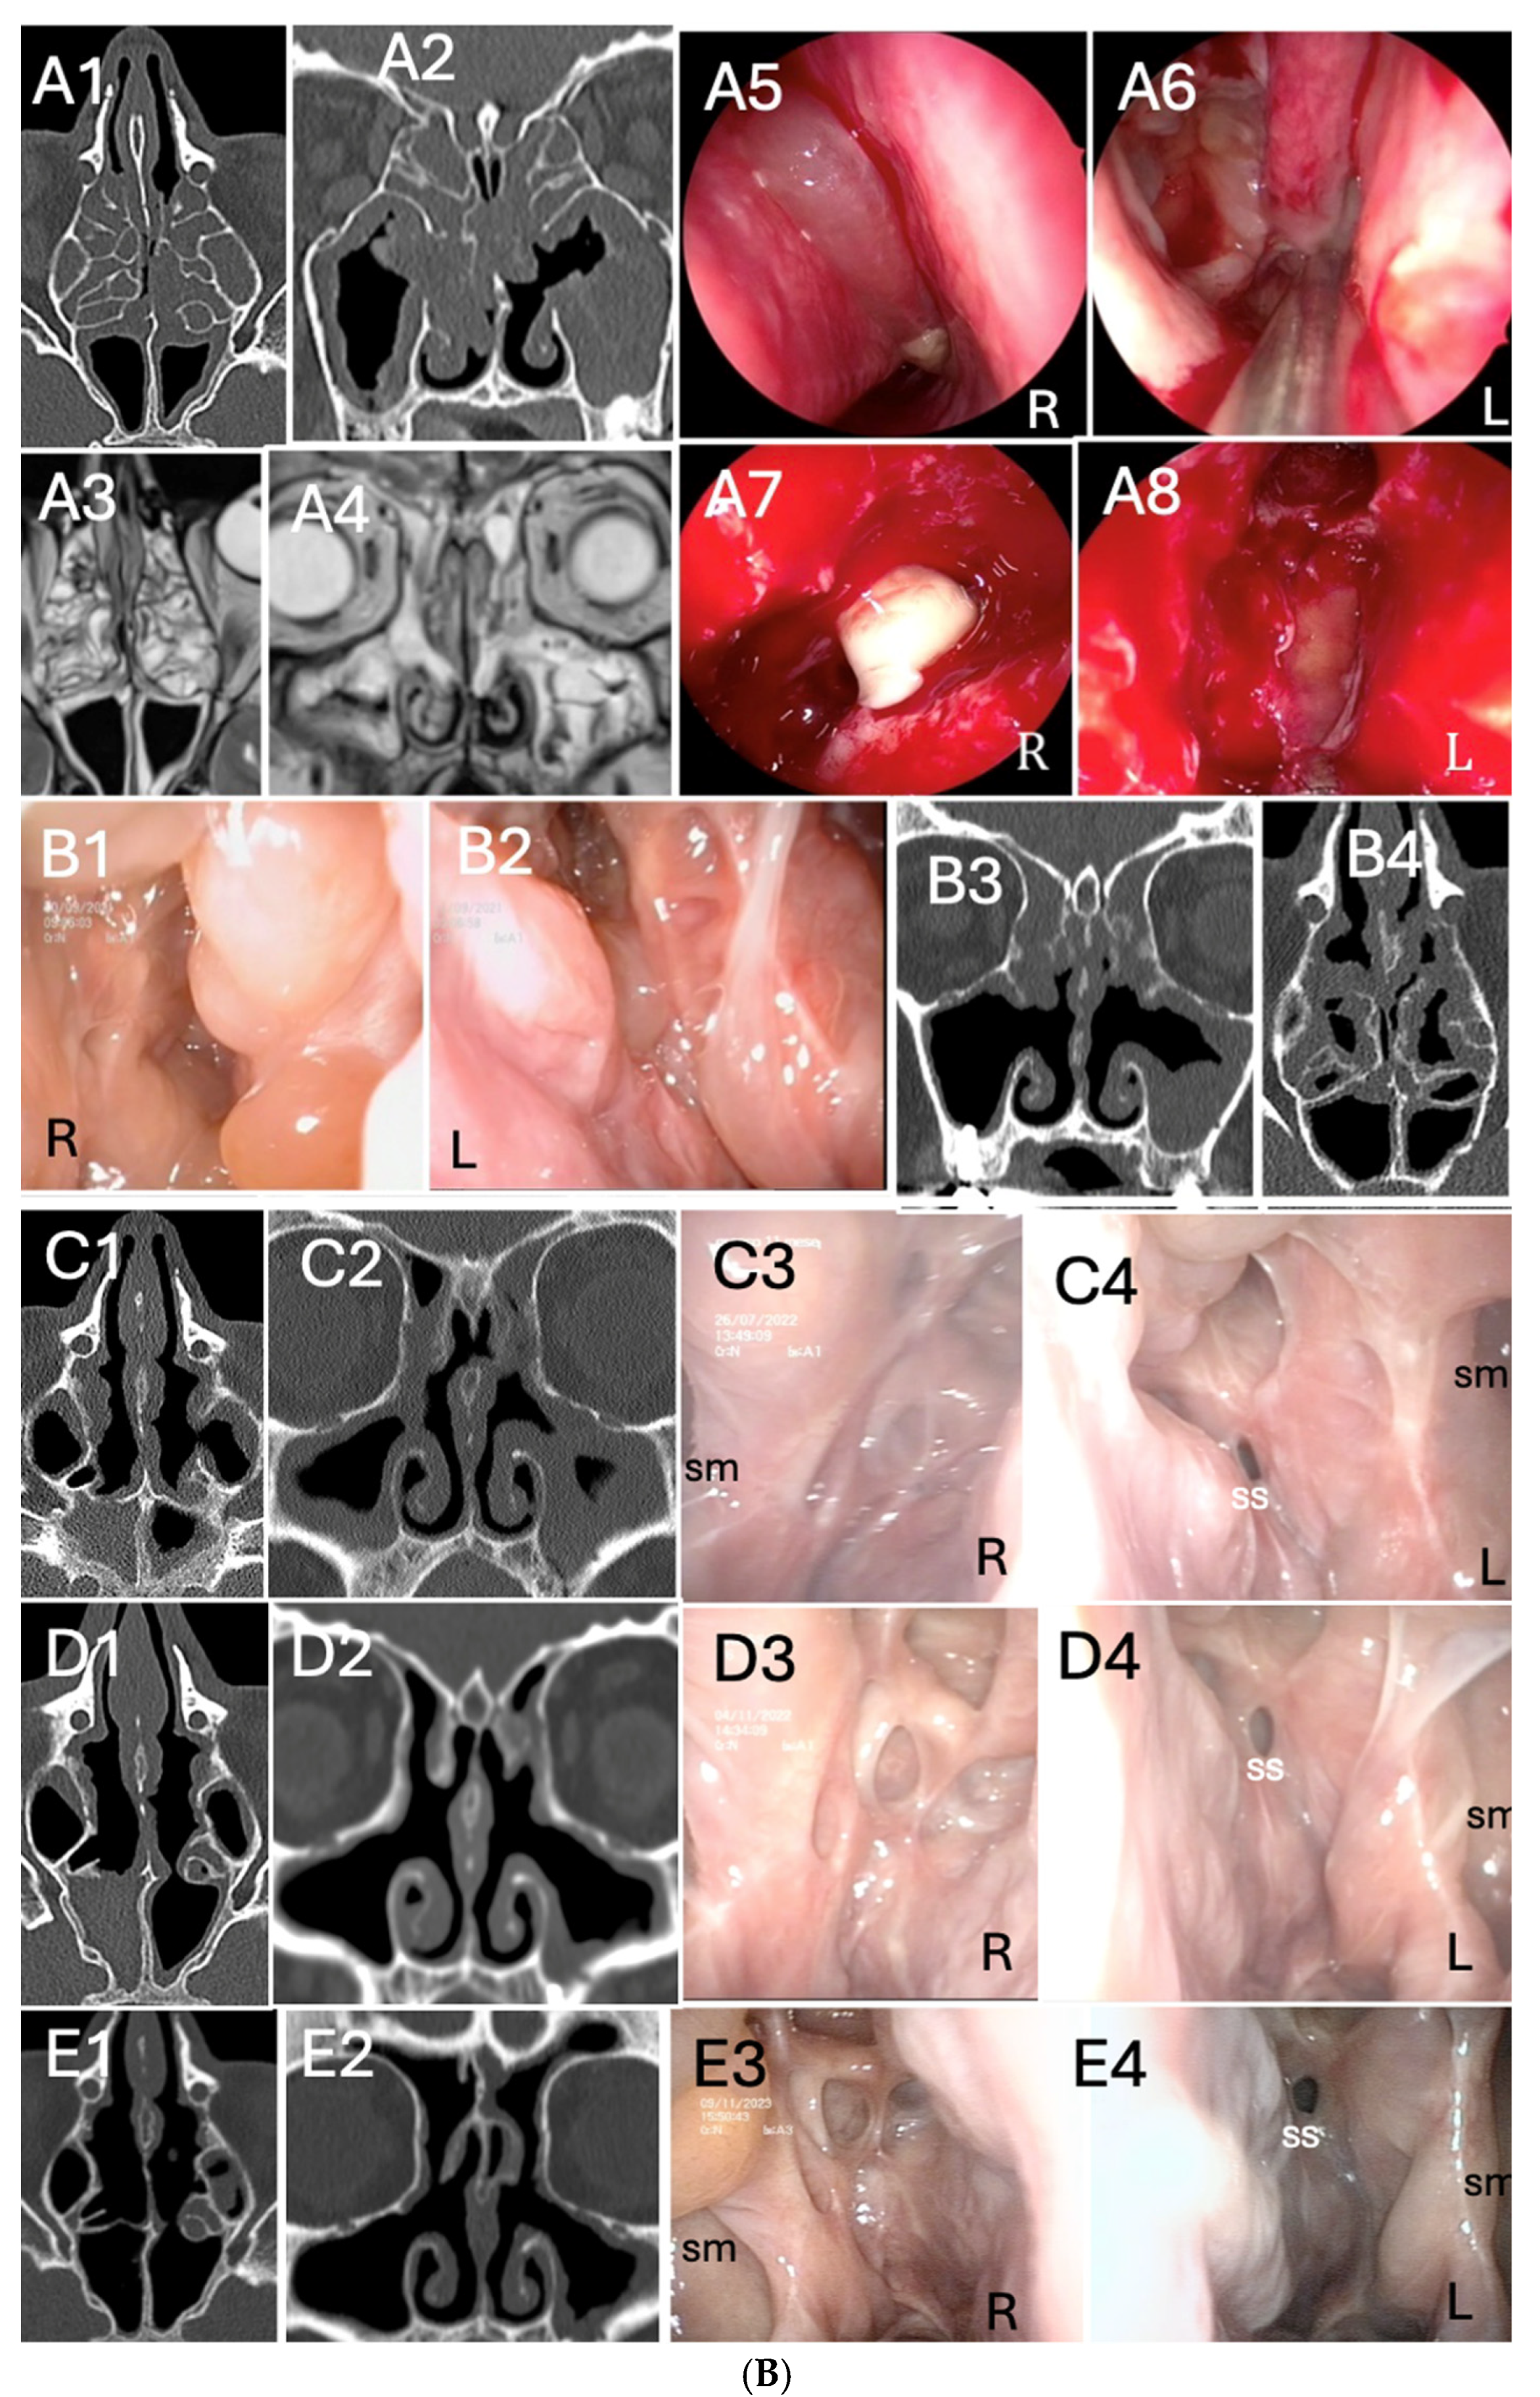

3.3. Clinical Response by Symptoms, Endoscopic, Radiologic Scores and Biomarkers Analysis During Follow-Up

3.4. Outcomes According to ACCESS Score Evaluation

3.5. Outcomes According to Previous Surgeries Stratification